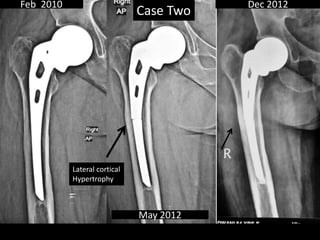

Case Two

• 54 years old Female

• AMP done out side.

• Had acute onset of anterior thigh pain May 2012.

• A suggestion was given to for Total Replacement

out side.

• Seen May 2012 with Broken Stem

• Full range free movements at hip

• Last seen Dec 2012.

Feb 2010

May 2012

Dec 2012

Lateral cortical

Hypertrophy

Case Two • 54years old Female • AMP done out side. • Had acute onset of anterior thigh pain May 2012. • A suggestion was given to for Total Replacement out side. • Seen May 2012 with Broken Stem • Full range free movements at hip • Last seen Dec 2012.

Feb 2010 May 2012 Dec2012 Lateral cortical Hypertrophy Case Two